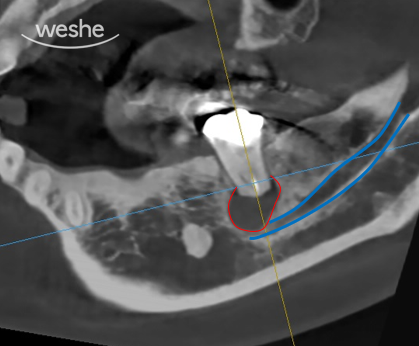

여러분이 보고 계신 사진은

치료를 마무리한 직후, 깨끗하게 정리된 뿌리 끝의 모습입니다.

환자분의 치아를 조심스럽게 입 밖으로 꺼낸 뒤,

고배율 환경에서 뿌리 끝 3mm를 정밀하게 치료하고

곧바로 원래 자리로 되돌려 심습니다.

이 과정을 의도적 치아 재식술 이라고 부릅니다.

왼쪽 사진은 치료 전, 오른쪽 사진은 치료 직후의 X-ray입니다.

보시면 뿌리 끝이 살짝 짧아졌고,

하얀색으로 채워진 치료제가 보이실 거예요.

“그런데 아직 뿌리 끝에 검은 그림자가 보이는데요?”라고 하실 수도 있습니다.